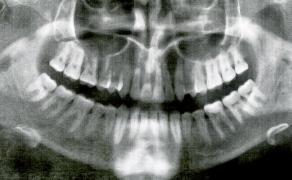

- Obrazowanie za pomocą zdjęć rentgenowskich.

Streszczenie: Chirurgicznie wspomagane poszerzenie szczęki (surgically assisted rapid maxillary expansion – SARME) stosowane jest przy leczeniu szkieletowych zaburzeń wymiarów poprzecznych szczęki u pacjentów dorosłych. Procedura ta oprócz poprawy warunków zgryzowych i estetycznych ma również wpływ na czynność układu stomatognatycznego – napięcie mięśni, funkcję języka i warg oraz oddychanie. Celem pracy było zgromadzenie współczesnych wyników badań na temat wpływu SARME na wymiary górnych dróg oddechowych na poziomie jamy nosowej oraz trzech pięter gardła. Do przeglądu piśmiennictwa zakwalifikowano oryginalne prace badawcze opisujące badania, w których zastosowano aparaty poszerzające szczękę, oraz dokonano oceny górnych dróg oddechowych za pomocą rentgenodiagnostyki, tomografii komputerowej, rynometrii akustycznej lub rynomanometrii. Przedstawione wyniki badań zwracają uwagę na wpływ leczenia ortodontyczno-chirurgicznego na struktury przestrzeni laryngologicznej, poprzez zwiększanie ich wymiarów. Długoterminowa stabilność tych zmian wymaga dalszych badań.